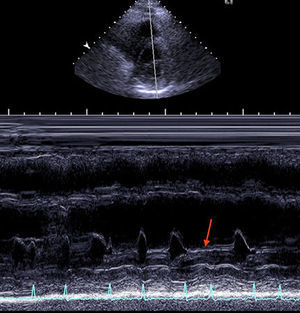

A 70-year-old man presented to the emergency department of our hospital with acute heart failure in the context of atrial fibrillation with rapid ventricular response (Figure 1). Physical examination revealed an irregular pulse, with moist rales in lung fields and lower extremity edema. In addition, a simultaneous electrocardiographic recording disclosed the absence of heart sounds during short diastoles. This finding of “silent” heartbeats led us to perform an echocardiogram, which revealed a left ventricular ejection fraction dependent on the R-R interval, which was normal during long diastoles and showed severe systolic dysfunction during short diastoles. M-mode recording of the mitral and aortic valves was carried out to acquire short-axis images from the parasternal window; they disclosed the failure of the mitral valve to open during short R-R intervals (Figure 2, arrow), as well as the failure of the aortic valve to open during the beat that followed (Figure 3, arrows).

To the best of our knowledge, there have been no previous reports of the presence of isovolumetric beats. Indeed, a reduction in diastole during short cardiac cycles has been documented in patients with atrial fibrillation. The present case report describes this phenomenon in what is probably its most extreme form, with the absence of ventricular filling and failure of the mitral valve to open during very short cardiac cycles. Likewise, the systole following the absence of ventricular filling was ineffective in mechanical terms, as shown by the failure of the aortic valve to open. This unusual echocardiographic finding is clinically relevant as it demonstrates that cardiac auscultation can underestimate the heart rate of patients with atrial fibrillation.